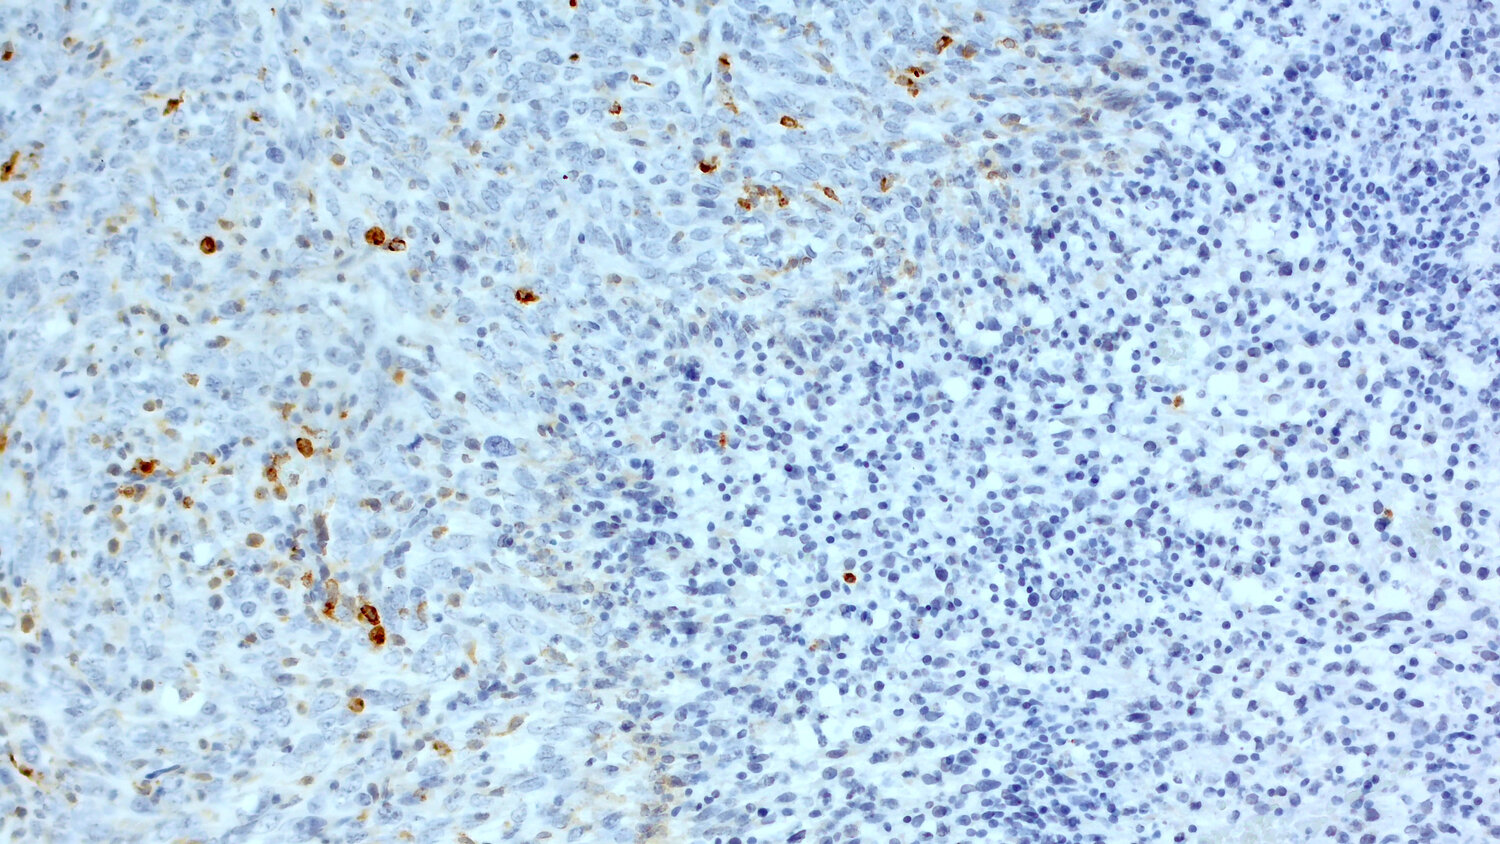

Antigen-presenting cells are important for the induction of anti-tumor immunity by priming naïve T-cells to differentiate into effector cells. As CD11c is highly expressed in human monocyte derived and in human conventional DCs, CD11c+ cells can be found in human tumors to be located in areas with high numbers of tumor-infiltrating lymphocytes (TILs). Therefore, high CD11c expression is associated with a longer median overall survival in patients e.g., with gastric cancer (Wang et al., 2015) or high-grade serous ovarian cancer (Corvigno et al., 2020). Furthermore, experiments in syngeneic mouse models in immunocompetent mice show that CD11c+ dendritic cells play a critical role in the tumoricidal activity of antibody therapies (Haynes et al., 2010). Therefore, histological detection of CD11c+ cells in syngeneic mouse models is an essential biomarker in pre-clinical oncology (figure 6).

Immunohistochemical staining for CD11c in formalin-fixed paraffin embedded sections of a murine breast cancer

Figure 6: Immunohistochemical staining for CD11c in formalin-fixed paraffin embedded sections of a murine breast cancer (EMT6; kindly provided by Charles River, Freiburg, Germany) using A anti-rabbit anti-CD11c (HS-375 003, 1:100; DAB) or B Guinea pig anti-CD11c (HS-375 004, 1:1000; DAB). Nuclei were counterstained with hematoxylin (blue).